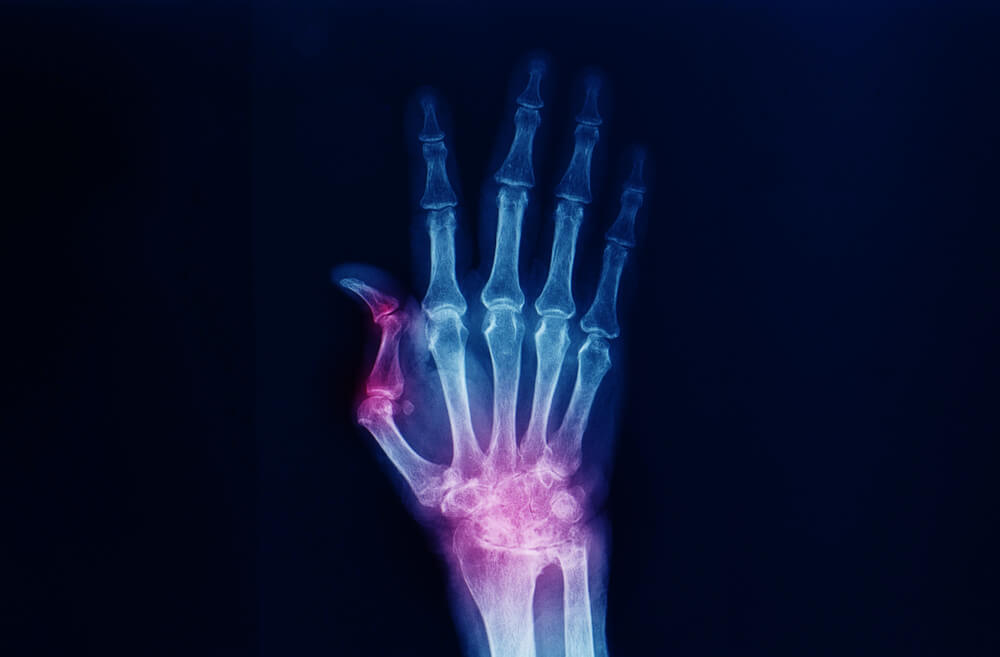

Bij artrose aan de duimbasis is het kraakbeen tussen de botjes versleten. Dit zorgt voor pijn bij knijpen, grijpen of draaien. Een brace zorgt voor stabilisatie en beperkt overmatige beweging. Hierdoor ervaart het gewricht meer rust, en dat helpt om de klachten te verminderen. Hierdoor kun je op een ondersteunende manier je dagelijkse werkzaamheden blijven uitvoeren.